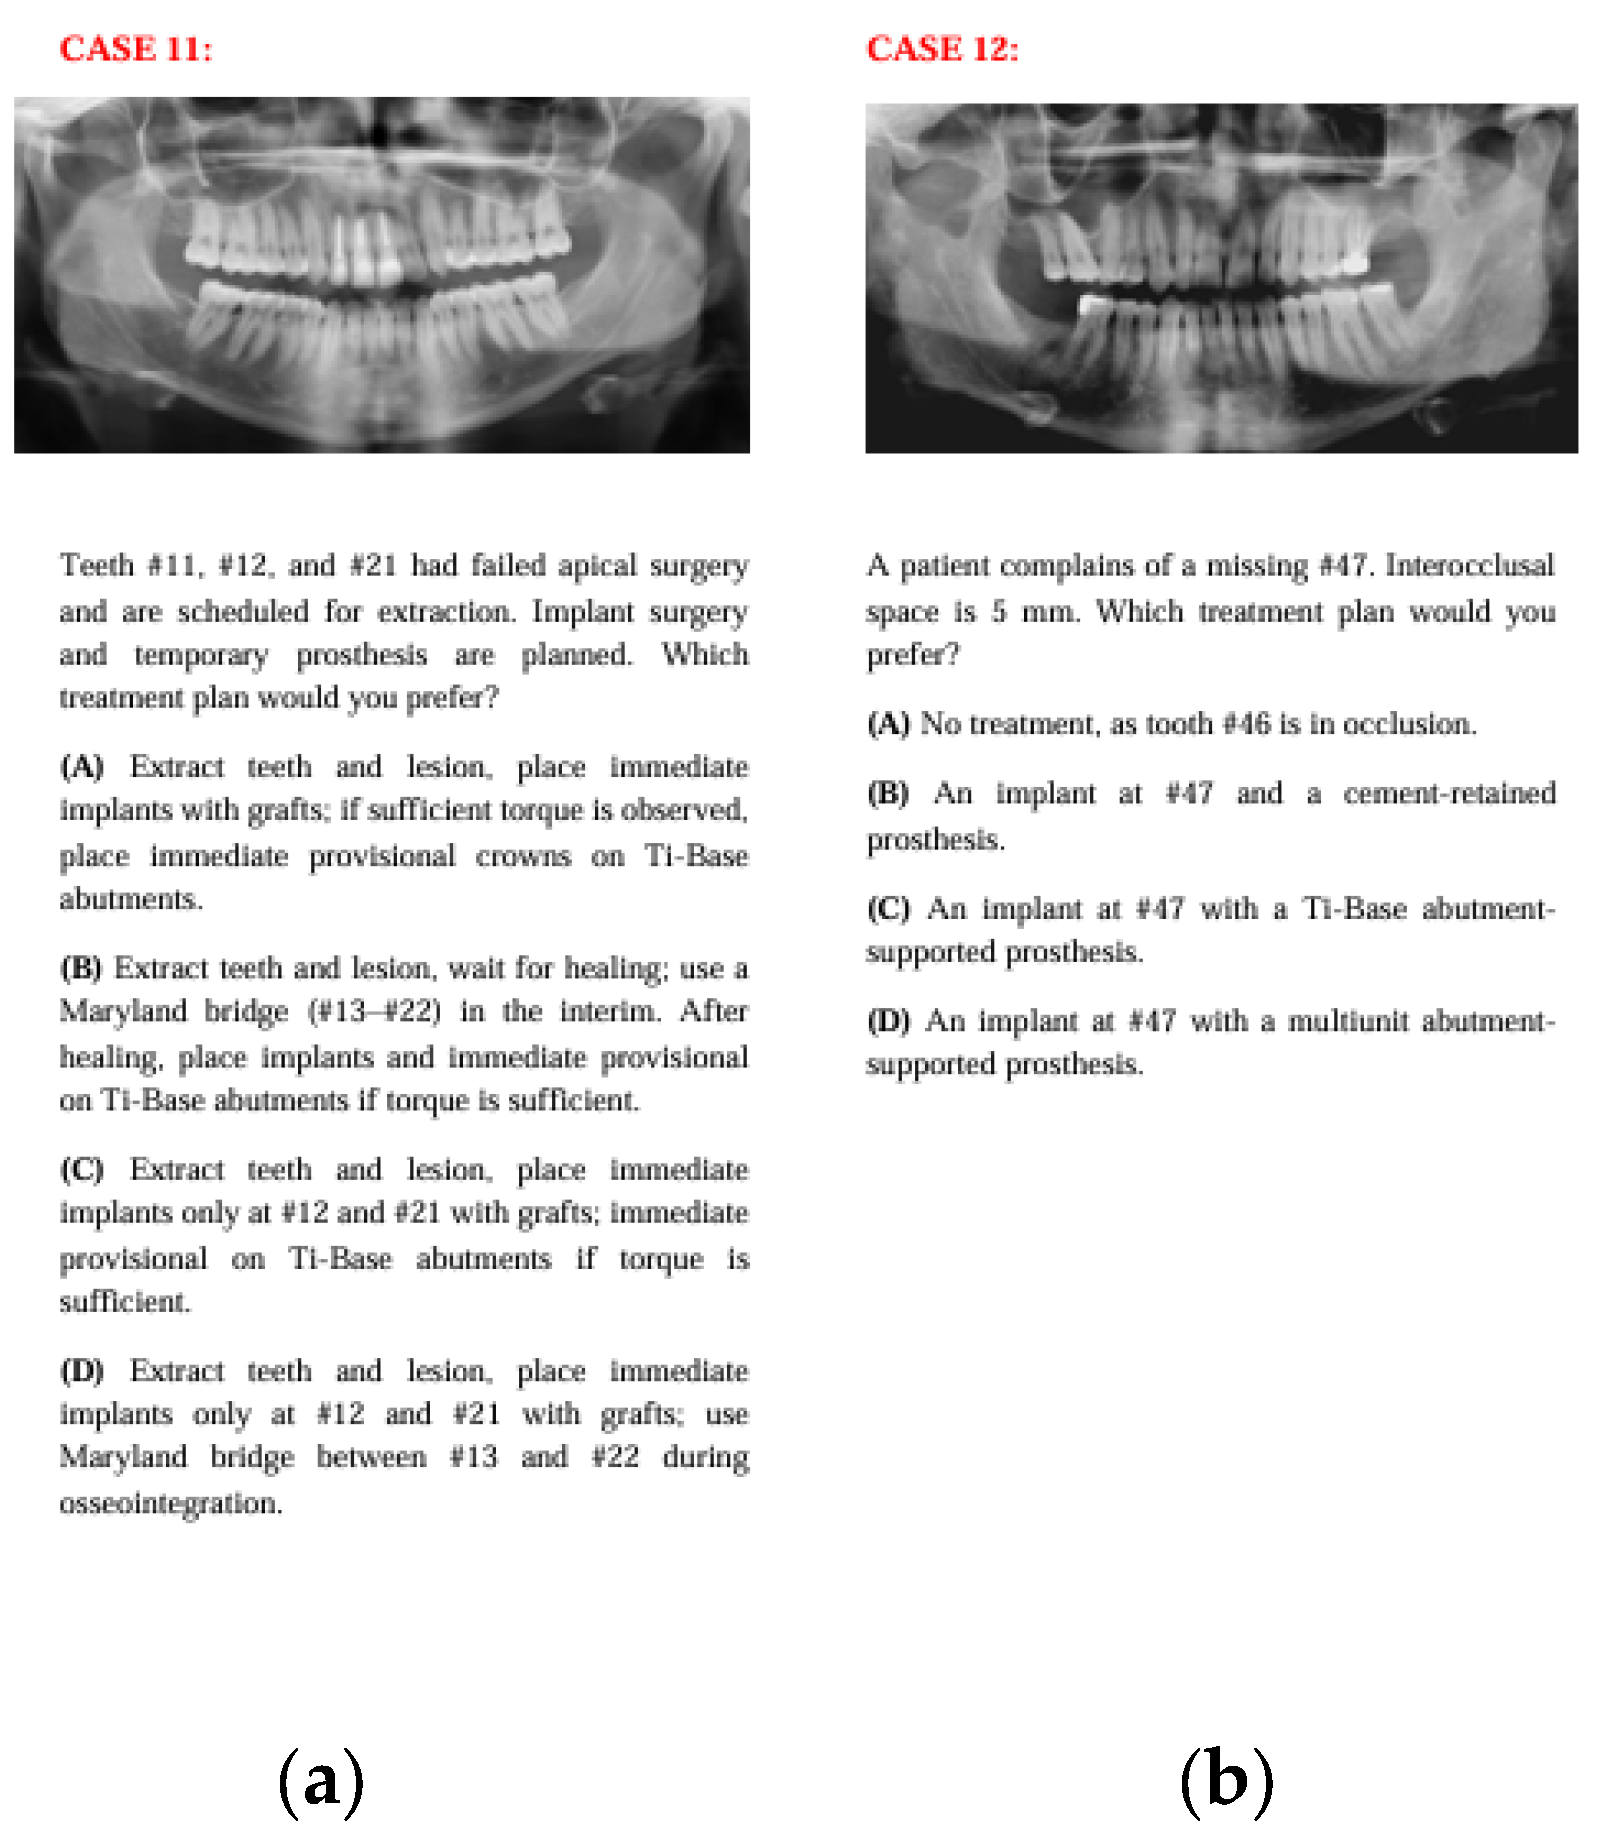

2.2. Case Scenario Preparation

Fourteen anonymized real patient cases with pre-implant surgery panoramic images were selected for the study. 14 cases were selected retrospectively from the patient records of the Department of Prosthodontics at Ankara University. The selection was performed jointly by one prosthodontist and one oral surgeon, based on representations of common clinical scenarios in implantology from simpler cases to more complex cases (single tooth loss, partial edentulism, and full-arch cases). Cases with poor radiographic quality, systemic contraindications, or unclear treatment history were excluded. To facilitate responses from both clinicians and the AI model, tomographic data, interocclusal distance, and other relevant surgical and prosthetic information were provided in written form, while only panoramic radiographs were presented visually. Due to the very large file sizes of cone-beam computed tomography (CBCT) datasets, which exceeded the upload limits, CBCT images were not provided; however, all clinically relevant three-dimensional information obtainable from CBCT was summarized within the case descriptions to ensure sufficient data for treatment planning. It was assumed that all patients mentioned in the case scenarios had good systemic health, adequate oral hygiene, and no financial restrictions for standardization. Clinical scenarios were prepared with four alternative treatment options for each case. The four management options for each case were drafted by one senior prosthodontist and one oral surgeon with >10 years of experience. The options were reviewed for clinical plausibility and to ensure that at least two alternatives represented commonly accepted approaches, while others reflected less preferred yet still clinically possible options (not intentionally wrong or contraindicated). The aim was not to distinguish “correct vs. incorrect” answers but to evaluate preference tendencies between clinicians and AI when faced with multiple feasible solutions. Scenarios included surgical parameters such as the number, size, location, and position of implants, the need for additional surgical procedures, and the placement protocol, as well as prosthetic factors including prosthesis type and number, location, abutment selection, material preferences, and loading protocols. Prosthetic and surgical considerations varied for each question. The panoramic radiographs, along with the case descriptions and four treatment options, are presented in Figure 1, Figure 2, Figure 3, Figure 4, Figure 5, Figure 6 and Figure 7.

Figure 6. The panoramic radiographs, descriptions, and four treatment options of Case 11 (a) and Case 12 (b).

In Case 11, where the case involved anterior esthetics and immediate implantation, clinicians predominantly chose options C and D, while AI chose option A. This may be because clinicians aimed to avoid the risk of placing implants across the entire area in an anterior region with a history of lesions or, guided by clinical intuition, leaned toward treatments with fewer implants or plans like option D that involve waiting for osseointegration to reduce complications. AI, on the other hand, may have leaned toward option A, which aligns with the current literature emphasizing the success of immediate implantation with immediate provisional prostheses in the esthetic zone, aiming to place as many implants as possible.

In Case 12, although option C was the most preferred across all groups, a significant distribution difference was found between human and artificial intelligence. In this question evaluating abutment types in single-implant restorations, clinicians, based on varied clinical experiences, opted for different choices, whereas AI consistently preferred single crown restorations on Ti-base abutments, which are frequently highlighted in the recent literature.